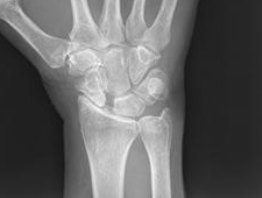

What are seen on a lateral xray for a SLAC wrist